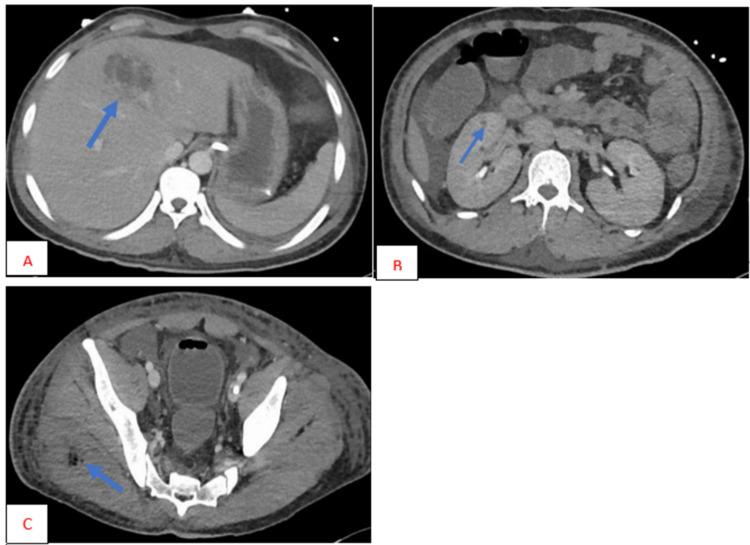

is a Gram-negative bacteria that can infect most of the body's organs, from the lungs to the central nervous system. It is notorious for causing pneumonia in alcoholic, diabetic, and hospitalized patients. It is now emerging as a cause of abscesses involving multiple organs. Invasive is most commonly observed in the Asian population but has been reported in other geographical areas as well. We present a case of invasive . The patient was initially admitted with diabetic ketoacidosis (DKA); further investigations showed multiple abscesses involving the liver, lungs, brain, and muscles. was identified in blood and liver abscess cultures. The patient was managed for DKA as per protocol, and was administered broad-spectrum antibiotics with percutaneous drainage of liver abscess for invasive syndrome. In this paper, we highlight the invasive nature of, which may aid clinicians in diagnosing and managing similar cases, thereby preventing the associated high morbidity and mortality.